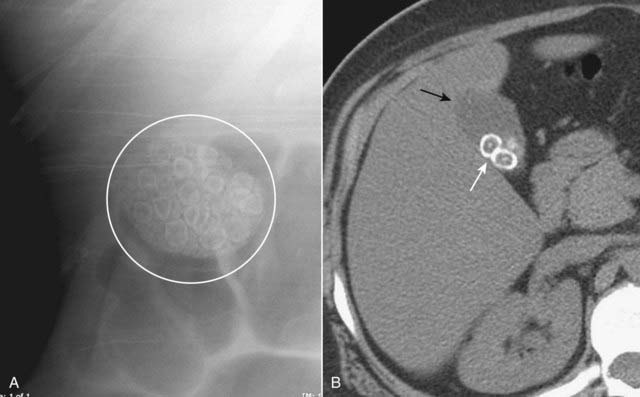

image

Figure 16-9 Gallstones, conventional radiograph (A) and axial CT scan (B).

A, There are multiple laminated calcifications (white circle) that have interlocking edges, suggesting that they all formed in a hollow viscus in proximity to each other. These are called faceted stones for their characteristic shapes. B, A close-up view of an unenhanced axial CT scan of the right upper quadrant shows several gallstones (solid white arrow), two of which clearly have a central nidus surrounded by laminated, concentric rings of noncalcified and calcified material. The gallbladder (solid black arrow) contains bile fats and is less dense than the liver.